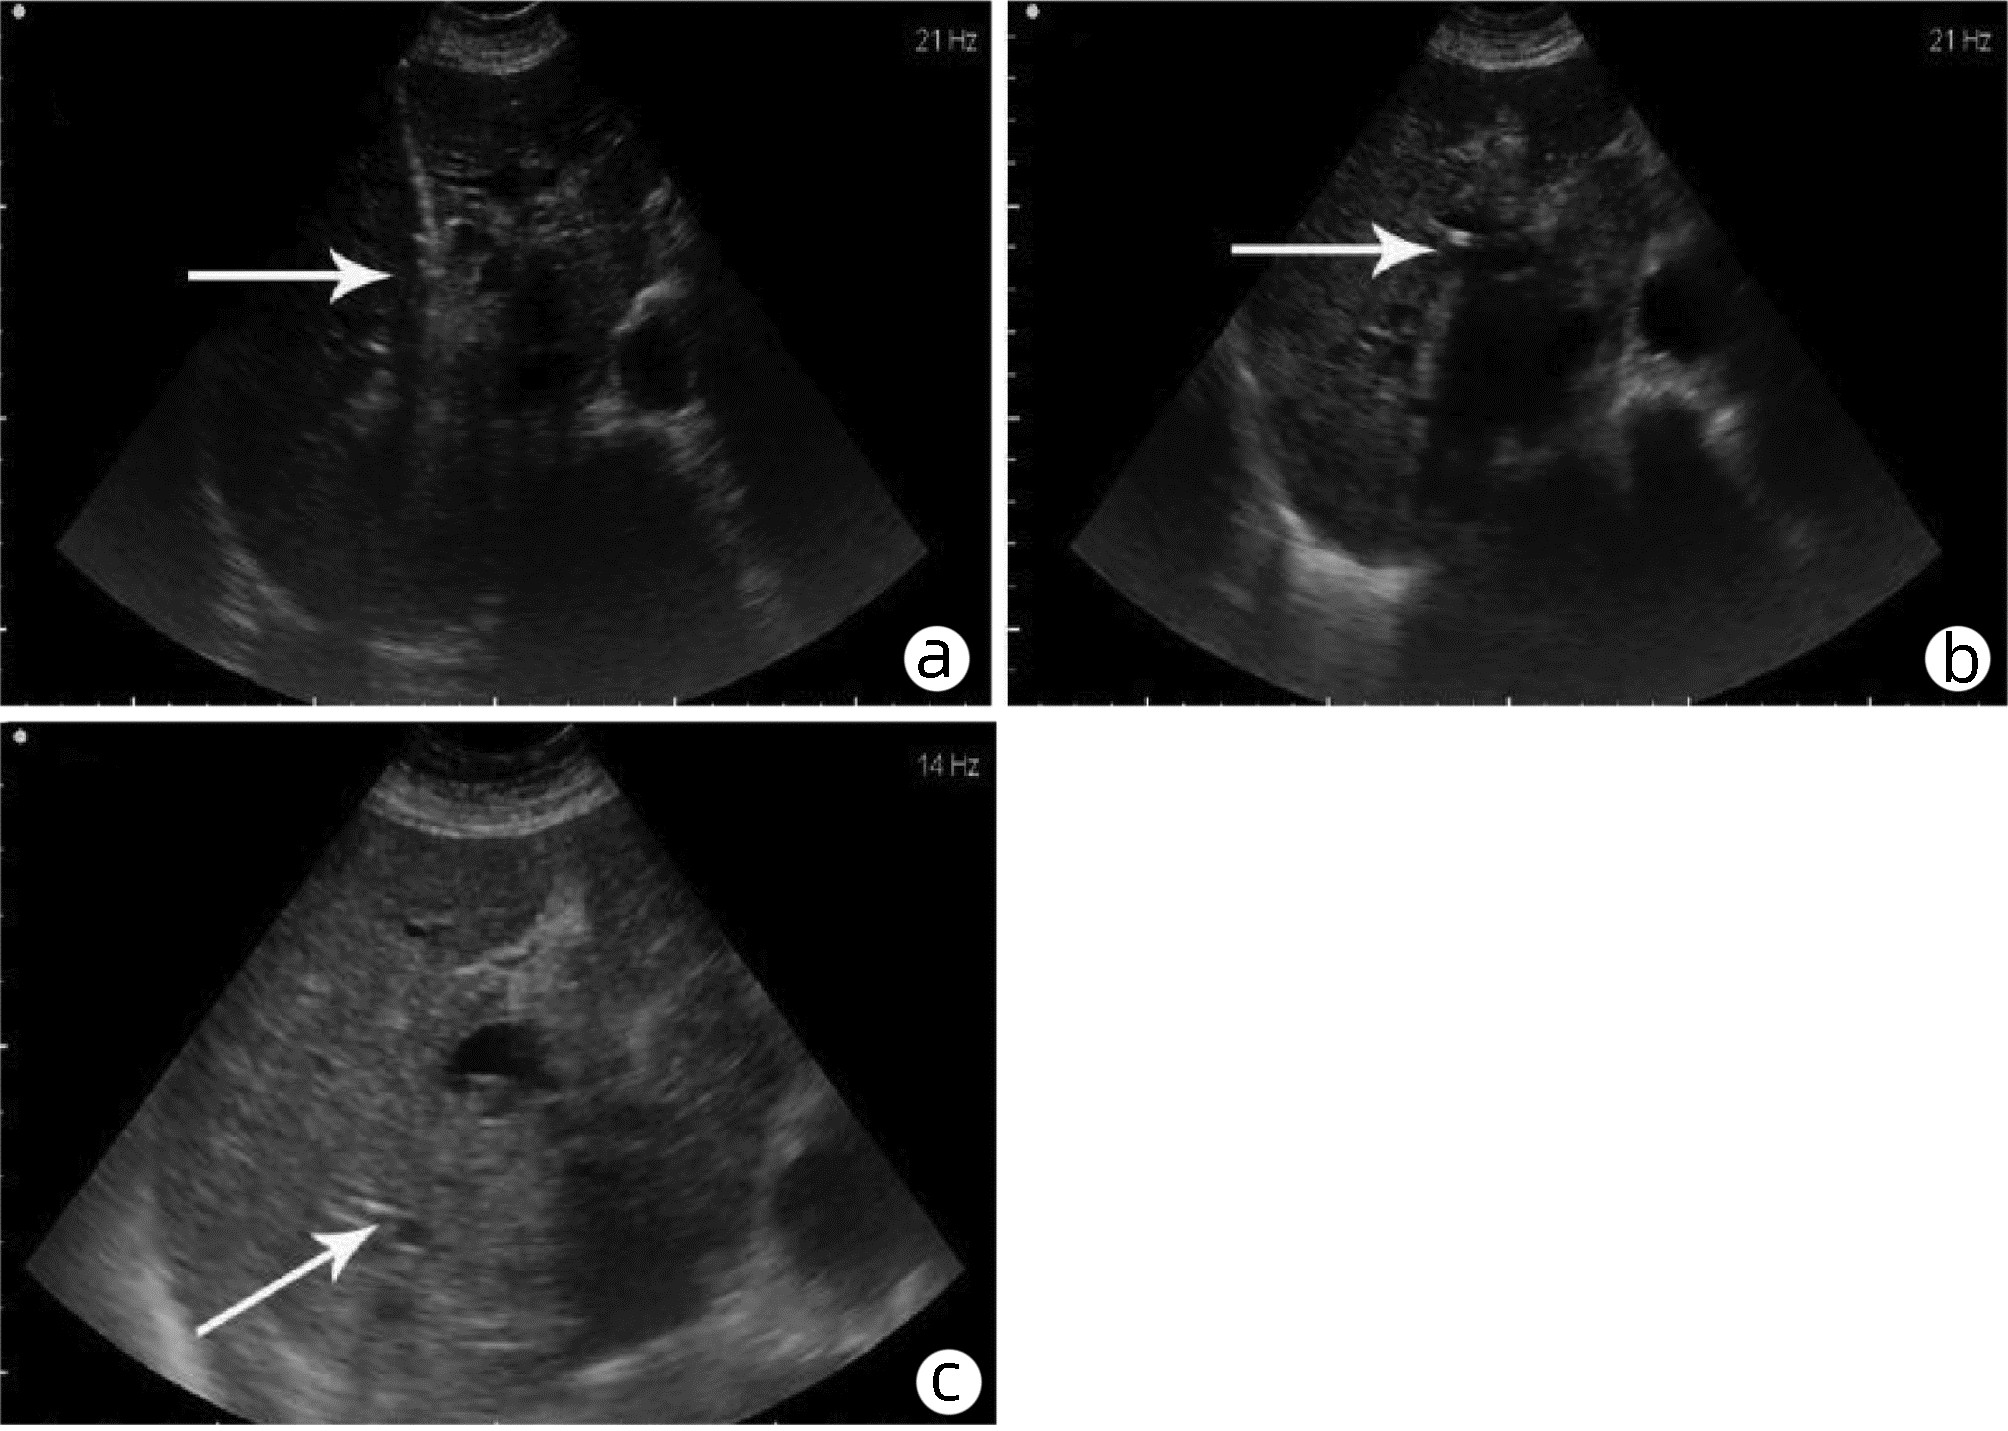

Application and clinical evaluation of ultrasound-guided biliary drainage tube replacement technology

Anhong ZHANG, Ruixin ZHANG, jie MA, Bo QIU, Xin YI, Zhihua LU, Lijie ZHENG, Hanguang DONG, Tian HAN, Li ZHANG, Yuanhui JIANG, Jun XU

2022, 38(11): 2542-2545. DOI: 10.3969/j.issn.1001-5256.2022.11.020

Abstract(1275) HTML (362) PDF (1987KB)(37)

Abstract:

Objective  To summarize the preliminary application results of ultrasound-guided biliary drainage tube replacement, present the corresponding technical points, and discuss the operation strategy and clinical application value.  Methods  The clinical data of 60 patients who underwent ultrasound-guided biliary drainage tube replacement in Qilu Hospital of Shandong University between August 2014 and August 2020 were retrospectively analyzed. The operation procedure, clinical applications, and postoperative complications were summarized and analyzed.  Results  Fifty-eight of the 60 patients (96.67%) were successfully replaced with drainage tubes along the original sinus. Among them, dilated sinus tracts of 47 patients were placed with coarse-grade drainage tubes, and dilated sinus tracts of the remaining 11 patients were placed with the original type of drainage tubes, with the mean operation time of 15.8(12.0-19.0) min under local anesthesia. In total, bile was drained from 28 patients receiving PTCD drainage, 23 patients receiving gallbladder drainage, and 9 patients receiving T-tube drainage. The post-operation evaluation revealed that the drainage situation has improved, with a 100% effective rate. No obvious abnormality was found in the postoperative follow-up visit.  Conclusion  The replacement of drainage tube under ultrasound guidance is simple, safe and feasible, and it provides further promotion in clinical practice with sufficient data support.